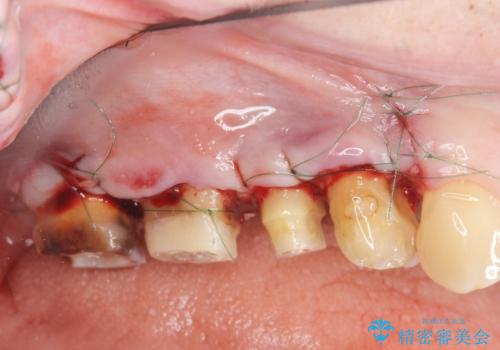

根管治療・歯周外科を行い歯を残した、複合的虫歯治療

- 近医で「根尖の病変が大きく、残すことができない、歯を抜くしかない。」、と言われ歯を抜く以外の手段がないかを相談しに来院されました。

検査の結果、根管・クリアランス・虫歯といった複合的な問題が認められ、以下のような治療計画を進めることとしました。

根尖病変 →マイクロスコープを用いた精密根管治療の実施

クラウンの製作スペースの付属 →歯周外科によるスペースの確保

機能の回復・再感染の予防 →精密なジルコニアクラウンの作製

一つ一つの工程を丁寧に行うことで、根尖病変の改善傾向も見られ、安定した歯周環境を整えることができました。